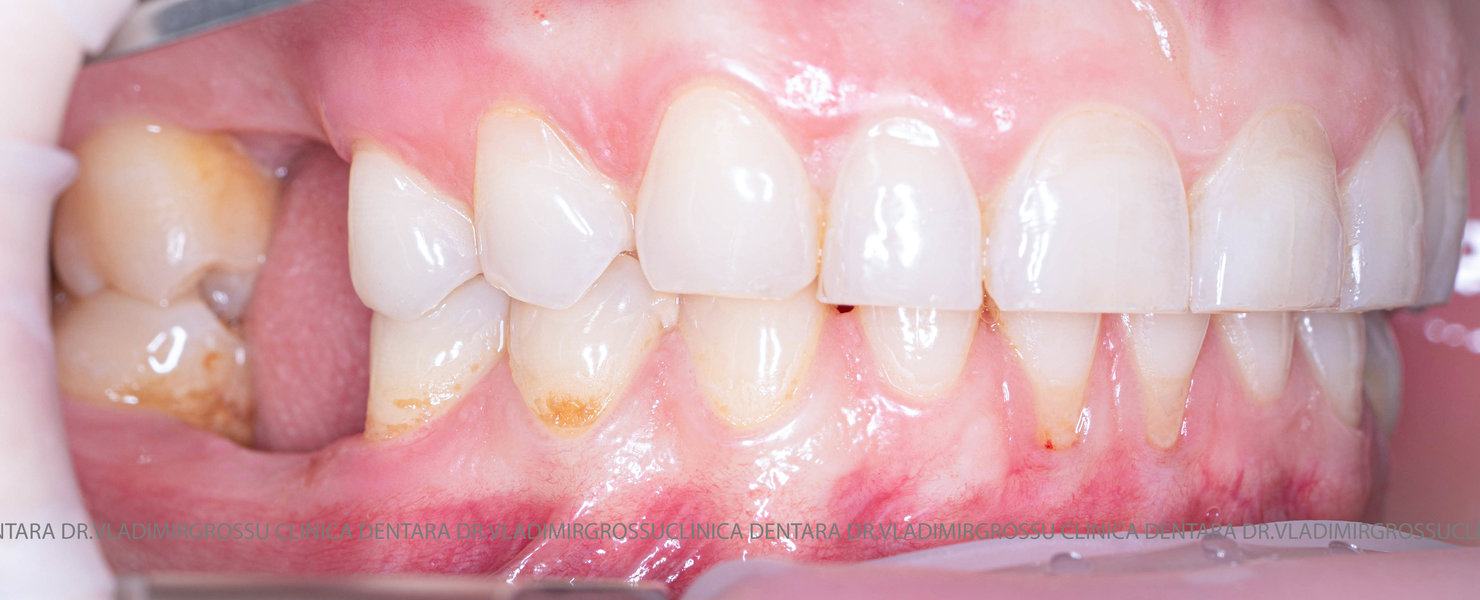

Aditia gingivală este o procedură chirurgicală ce corectează diverse probleme estetice și funcționale, cum ar fi recesiunea gingivală. În implantologia modernă, aditia de țesut moale este utilizată aproape în fiecare intervenție de inserție a implantului dentar pentru a asigura un aspect estetic natural și o bună integrare a implantului în cavitatea bucală.